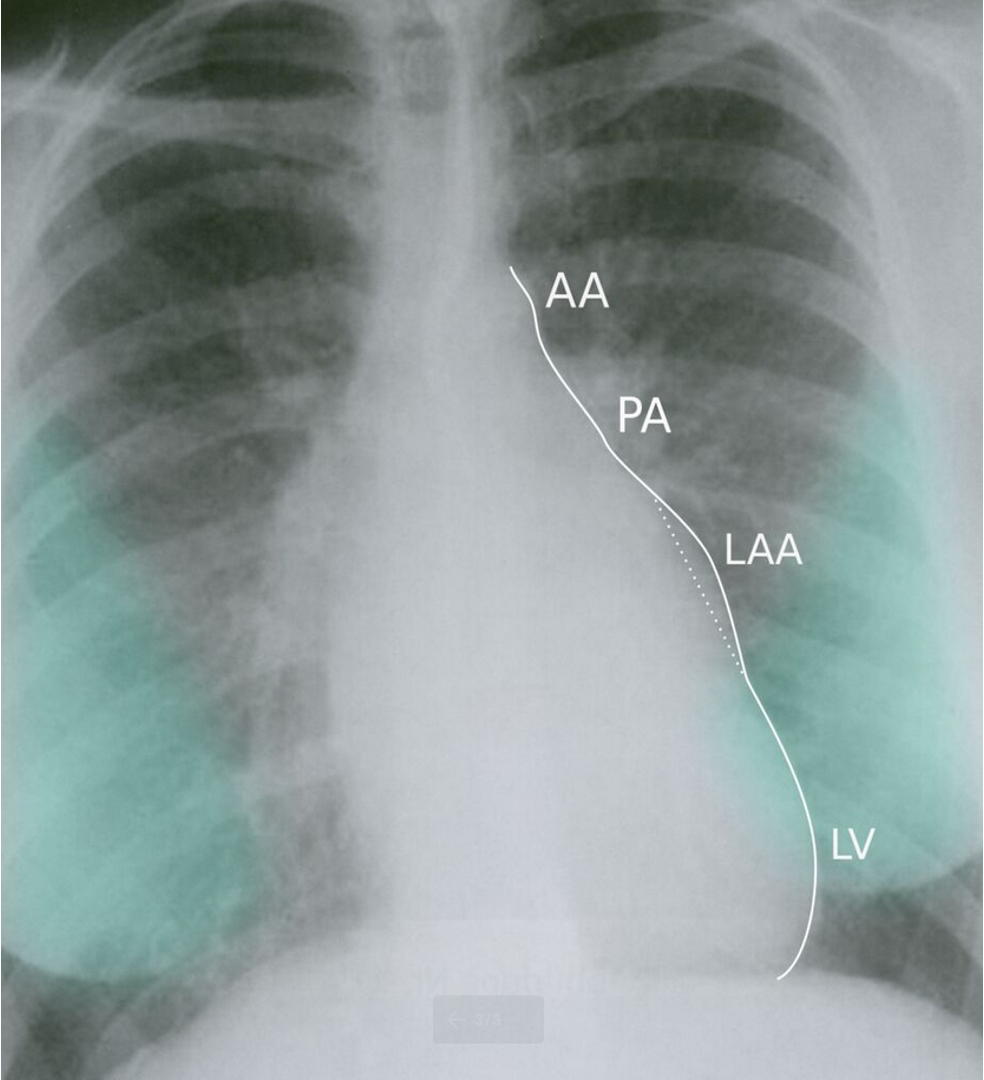

CXR Z

-

Left atrial enlargement

Mitralisation of heart: straightening of left heart border

Elevation of left mainstem bronchus

Evidence of mitral calcification

Evidence of pulmonary edema kerley’s b lines

Double contour of the right border of heart

PA view: ⇒ Left atrial enlargement:

- Convexity or straightening of the left atrial appendage.

- Left heart border is straight or convex

- Double density of RTÂ cardiac border

- Elevation of the left main bronchus and splaying of the carina

LA view: posterior protrusion of the upper part of posterior heart border.